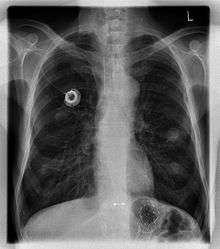

Chest X-ray showing an implanted port.

The port is usually inserted in the upper chest (known as a "chest port"), just below the clavicle or collar bone, leaving the patient's hands free.

Ports can be put in the upper chest or arm. The exact positioning itself is variable as it can be inserted to avoid visibility when wearing low cut shirts, and to avoid excess contact due to a backpack or bra strap. The most common placement is on the upper right portion of the chest, with the catheter itself looping through the right jugular vein, and down towards the patient's heart.